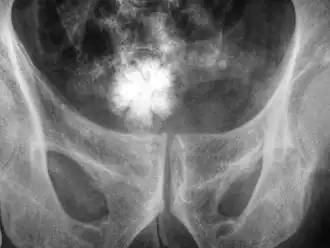

![]() Radiografía de la pelvis con un cálculo en forma de estrella en la vejiga urinaria. | ||